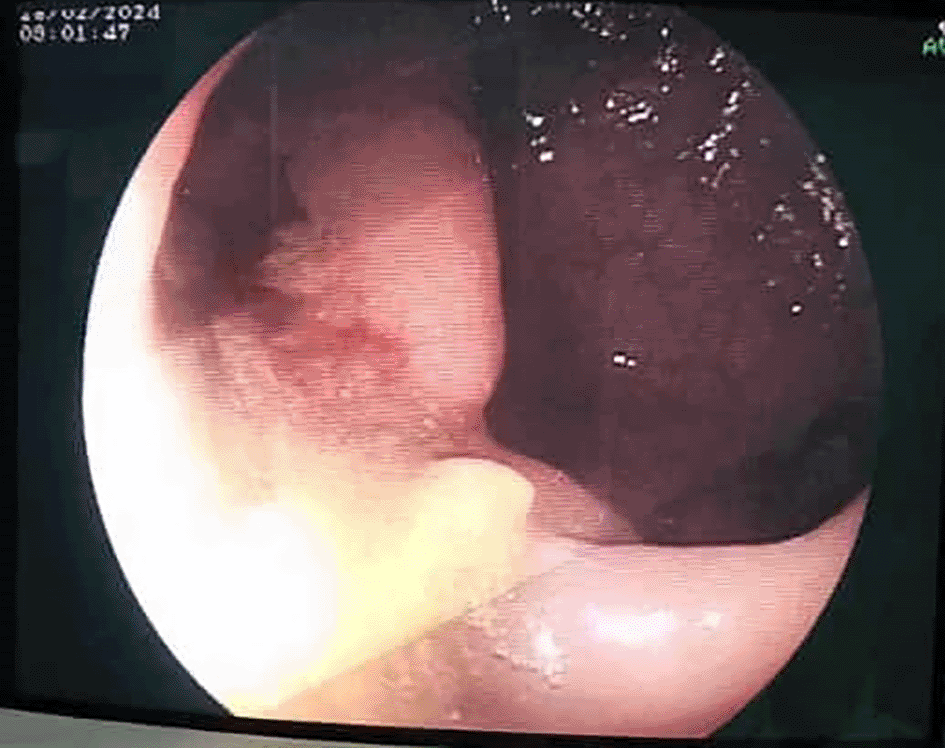

On day 13 of continuing intravenous antibiotics, the patient reported a sensation of rectal fullness. Rectal exam revealed a textile foreign body soiled with feces. An abdominal CT scan was ordered. It confirmed the progressive migration of both foreign bodies, described in a heterogeneous mass containing gas bubbles and air-filled linear or wavy radiodensities, along the colon, one reaching the transverse colon and the other component extended toward the rectosigmoid and externally protruded distally through the anal margin (Figure 3). Rigid rectoscopy on day 18 confirmed retained gauze embedded in the rectal mucosa approximately 20 cm from the anal verge (Figure 4), which was extracted under visual guidance (Figure 5). Following extraction, the patient developed acute diffuse abdominal pain and guarding.